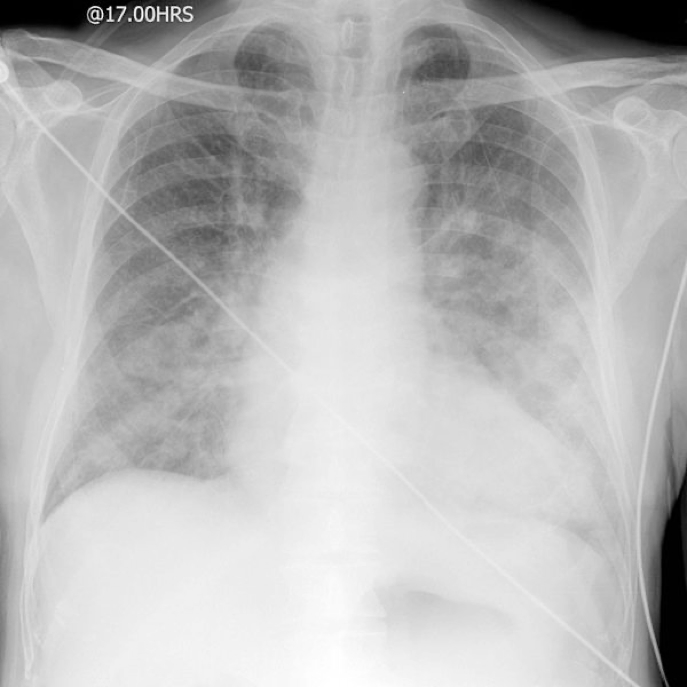

Pulmonary Embolism

- Foreign material obstructing a pulmonary vessel.

- Most commonly blood clot (thrombus).

- Prevents oxygenation of blood in affected region.